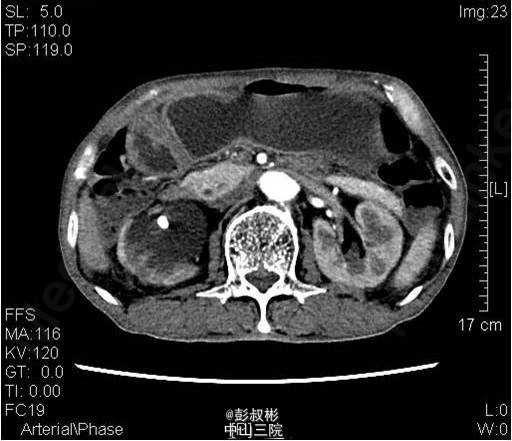

3、既往病史:既往“高血压”病史20年余,自服硝苯地平。“脑梗死”病史半年余,规律服用抗凝药物。 4、入院查体:无明显阳性体征。 实验室检查: 2015-01-11 肌酐101.2umol/L 。 2015-01-13总前列腺特异性抗原1.1ng/ml,游离前列腺特异性抗原0.3ng/ml。 2015-01-15 白细胞总数3.21x10E9/L,红细胞总数2.61x10E12/L,血红蛋白浓度78g/L,肌酐131umol/L ,白蛋白27g/L。 影像学检查: 2014-12-30心电图:完全性右束支传导阻滞。 2014-12-30全腹螺旋CT 检查所见:1、前列腺增生并钙化,建议MRI增强进一步检查除外合并肿瘤性病变。2、右侧盂管交界处结石并重度梗阻性肾积水,右肾结石;左肾多发钙化灶;左肾多发囊肿。3、慢性胆囊炎。4、双肺下叶多发小结节。 2015-01-14核素肾动态显像+GFR双血浆测定:右肾灌注、功能重度受损。左肾灌注正常,功能中度降低。肾小球滤过率:左肾为23.4ml/min,右肾为9.0ml/min。 2015-01-15彩超心脏:二尖瓣反流(轻度)。三尖瓣反流(轻度)。左室收缩功能正常。左室舒张功能减退。

5、目前诊断:1、右侧重度肾积水2、双侧肾结石3、左肾多发囊肿4、慢性胆囊炎